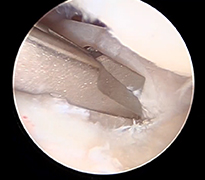

El bileği artroskopisi, el bileği ekleminin küçük kesilerden girilerek kamera ve özel cerrahi aletler yardımıyla değerlendirilmesi ve tedavi edilmesini sağlayan modern bir yöntemdir. Bu teknik sayesinde eklem içi yapılar detaylı şekilde görüntülenebilir. Özellikle bağ yaralanmaları, kıkırdak hasarları, TFCC (üçgen fibrokartilaj kompleks) lezyonları ve bazı kırık sonrası problemlerinin tanı ve tedavisinde kullanılır. Hastalar genellikle el bileğinde ağrı, hareket kısıtlılığı veya tıklama hissi ile başvurur.

Artroskopik yöntem, açık cerrahiye göre daha küçük kesilerle yapıldığı için doku hasarı daha azdır ve iyileşme süreci genellikle daha hızlıdır. İşlem sırasında hem tanı konulabilir hem de gerekli onarımlar aynı seansta gerçekleştirilebilir. Ameliyat sonrası kısa süreli istirahat ve ardından kontrollü egzersiz programı önerilir. Uygun hastalarda el bileği artroskopisi, ağrının azaltılması ve fonksiyonun geri kazanılması açısından etkili ve güvenilir bir tedavi seçeneğidir.